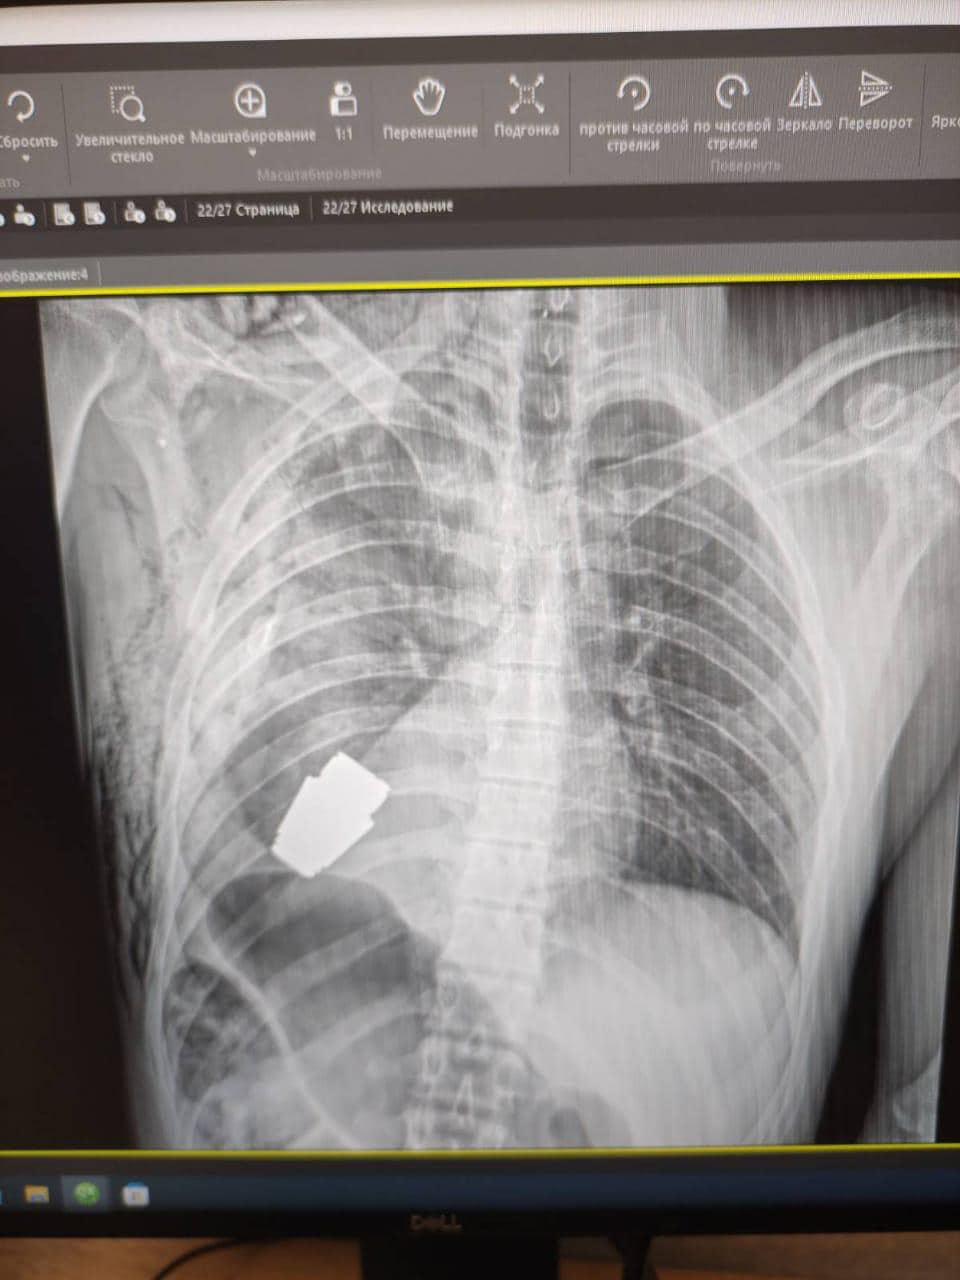

Malyar posted an image to Facebook apparently showing the X-ray of the “VOG grenade” inside the soldier’s body, just beneath his heart. VOG grenades are about four centimetres long and can be fired a distance of about 400 metres.

Maj. Gen. Andrii Verba, who is described in the post as one of Ukraine’s “most experienced surgeons,” performed the delicate extraction without the use of electrocoagulation, which is a common surgical method to control bleeding, because of the risks it posed in this exceptional circumstance.